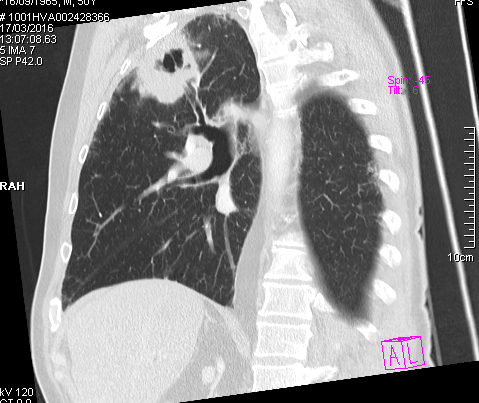

Obtenemos las siguientes imágenes en distintos planos:

Vemos que la estructura cavitada posee una pared muy gruesa, más típica de un proceso neoplásico, y una cavidad hipodensa. Confirmamos su localización en el lóbulo superior derecho y anterior. Descartamos proximidad a vasos y estructuras mediastinicas, así como invasión de la pared torácica. Y lo mas importante es que apreciamos que el bronquio principal mas proximal a la masa cavitada, el bronquio anterior del lóbulo superior derecho, se encuentra amputado cuando llega a la masa y no comunica con la cavidad del interior de la masa,